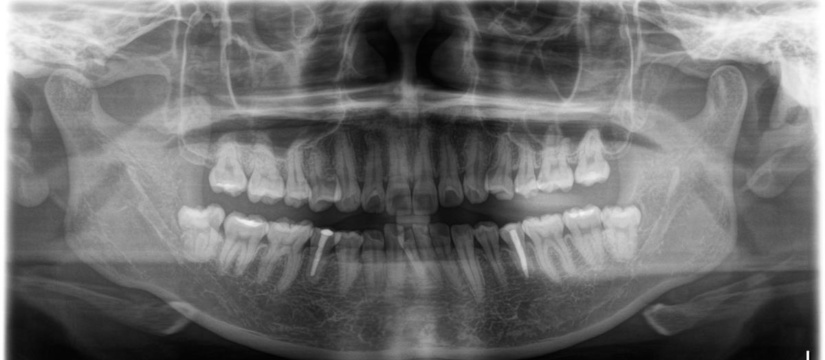

虫歯、歯周病などの慢性疾患はもちろんのこと、親知らずの抜歯や顎関節症などの疾患のみならず、ホワイトニング、セレックによるセラミック治療、インプラントなどにも対応しております。口腔外科や耳鼻咽喉科などのクリニックとも提携しておりますので、お口の中でお困りのことがあればご相談ください。

我々の分野は数ミクロンというとてつもなく小さな細菌との戦いです。虫歯も歯周病も細菌が引き起こす感染症なのです。マイクロスコープを用いても細菌が見えるわけではないのですが、根の中や歯周ポケット内部などは肉眼では到底はっきり見ることはできず、被せ物がどれだけぴったり合っているかなども肉眼出判別するには限界があります。マイクロスコープは治療の精度を格段に向上させることができます。保険保険外に関わらず、マイクロスコープが有用と判断された場合に使用しております。